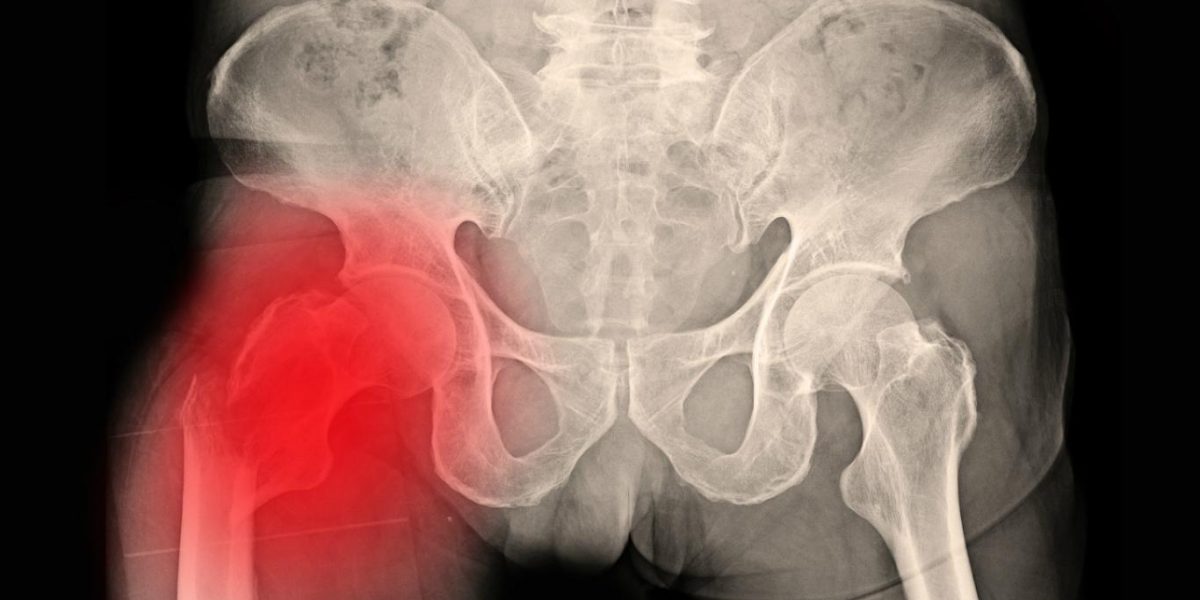

¿Sabías que el 90% de las fractura de cadera se dan en personas mayores de 64 años? En una revisión que se hizo en España, se encontró que en tres años (entre 1996 y 1999) hubo 147.066 fracturas de cadera. De estos casi 150 mil pacientes, 130 mil eran iguales o mayores a 65 años. ¿Cómo podemos ayudar con una fractura de cadera si un familiar nuestros se ha caído? Te lo contamos

¿Cuál es la gravedad de una fractura de cadera?

La fractura de cadera, al hablar de ancianos, puede ser una patología un tanto complicada. No por la fractura en sí, sino por todo lo que conlleva: pasar por quirófano, hospitalización, rehabilitación, pérdida de independencia… Aquí hablamos largo y tendido sobre la Fisioterapia Geriátrica y cómo puede ayudar en estos casos.

En ancianos, cuando hay fractura de cadera y hay que operar, la estancia media en el hospital varía desde los 12-13 días de la Comunidad Valenciana, hasta los 23-24 días de Canarias. Si hablamos de la mortalidad asociada a esta patología, se calcula que la mortalidad hospitalaria global es del 5%. Igualmente, varía mucho según las comunidades: 2-3% en la Comunidad Valenciana, o incluso un 7-8% en Aragón. Es importante destacar dos aspectos:

- La mortalidad asociada a la fractura de cadera es casi el doble en los hombres que en las mujeres (8,1 vs 4,2 respectivamente),

- La mortalidad aumenta con la edad en ambos sexos, pudiendo llegarse a situar en el 16,9% en hombres y el 10,9% en mujeres de más de 99 años.